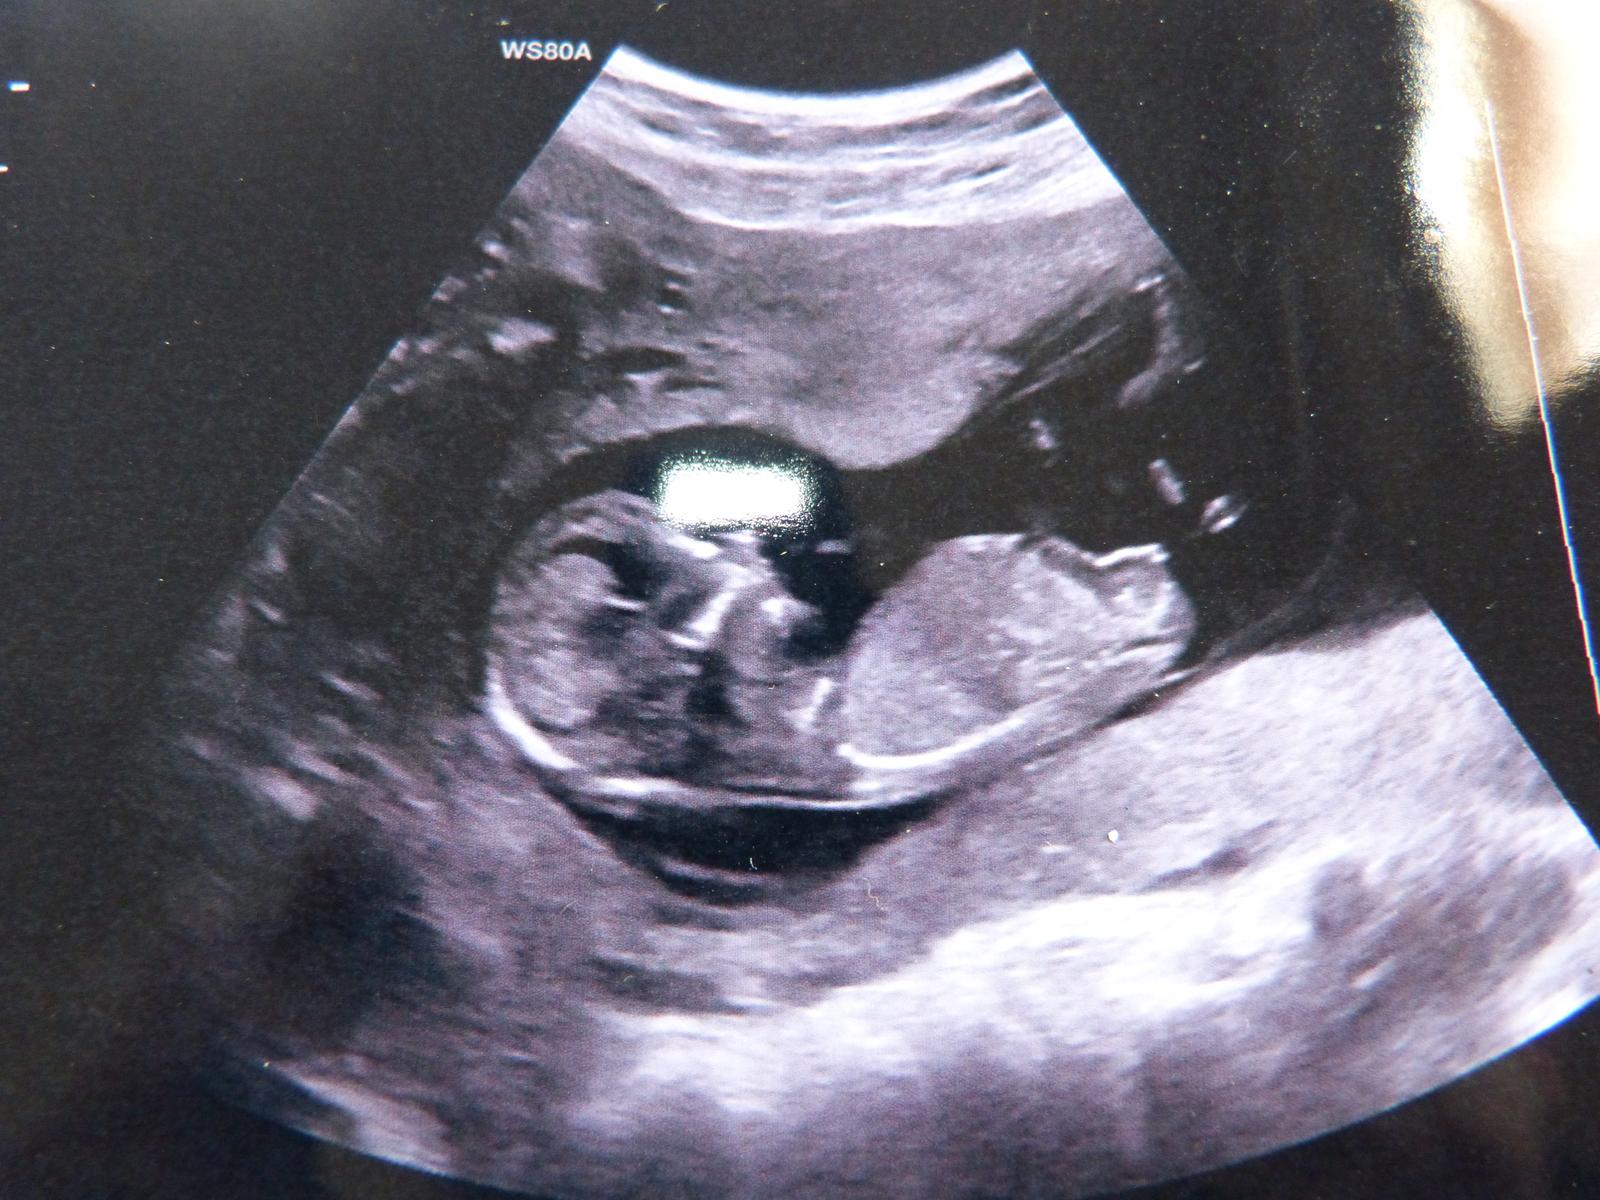

AHOJ, PRIKLADAM DVE FOTECKY ZE SCREENINGU.. OBE 13 + 1... PRVNI FOTO JE NAS DVOULETY CHLAPECEK.. JE VIDET VYBEZEK NAHORU, DRUHE FOTO , JE MIMINO, KTERE MAM TED V BRISKU.. DLE LEKARKY TO VYPADA NA HOLCICKU.. A JA ZATIM ASI MOHU SOUHLASIT..... NA DRUHE FOTCE VYBEZEK NAHORU NENI.... TAK OPET UVIDIME ZDA MI TO MA LEKARKA ZA TRI TYDNY POTVRDI...